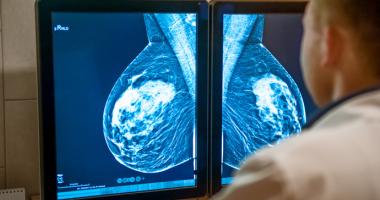

Cirugía reconstructiva de las mamas y los implantes

Preventivos: mamografía y sonomamografía; mastectomía